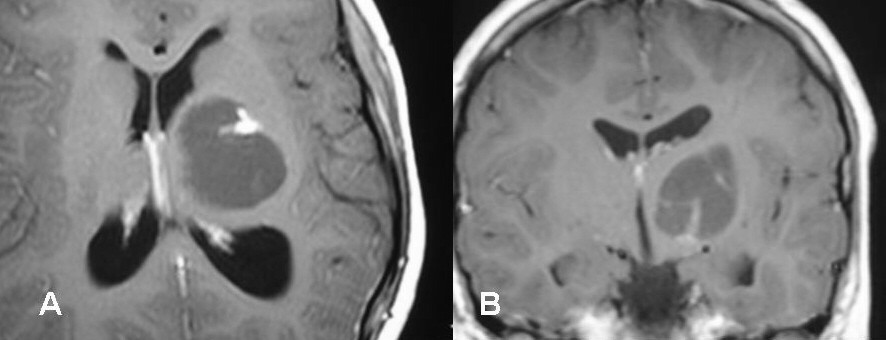

Get Brain Tumor Biopsy Results Time Images. At times, it is supplemented by a magnetic resonance spectroscopy (mrs), which provides information about the chemical composition of the tumor. Sometimes doctors will remove a brain tumor and then perform a biopsy to get more information about the tumor.

Making the diagnosis without a biopsy. Your outcome is determined by such factors as the tumor's type, grade, and location; Some people have a biopsy at the same time they have brain we know it's a worrying time for people with cancer, we have information to help. Making the diagnosis without a biopsy.